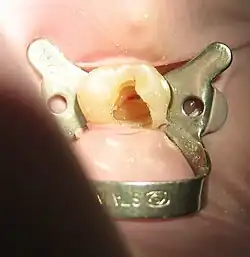

![]() Tooth #13, the upper left second premolar, after excavation of DO decay. There was a carious exposure into the pulp chamber (red oval), and the photo was taken after endodontic access was initiated and the roof of the chamber was removed. | |